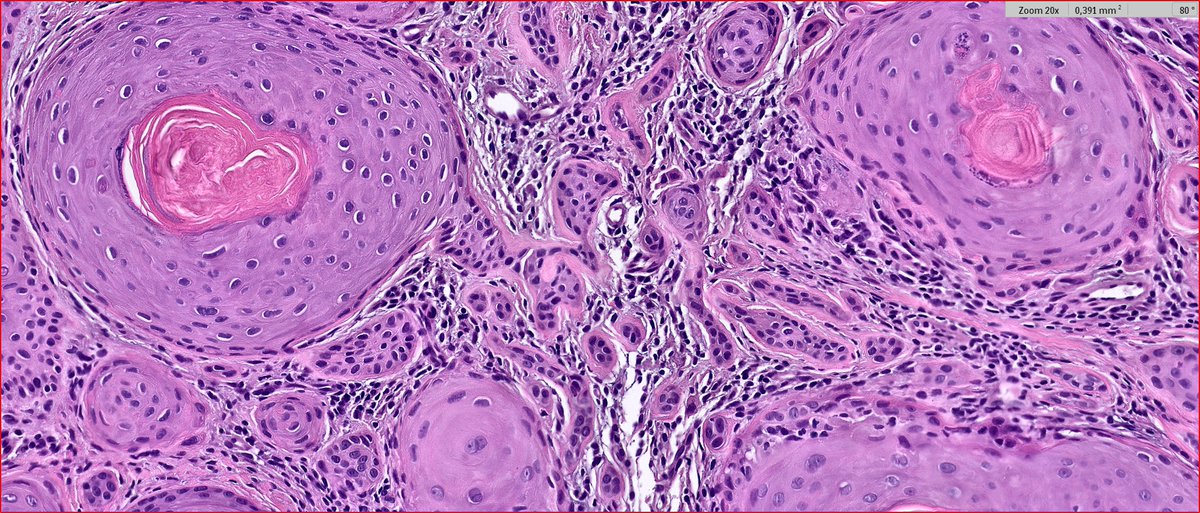

2024 Wk46 ish! RAC9183. M80s Right temple lesion. Previous skin cancers. #TooFarToDiagnose ? #Dermpath